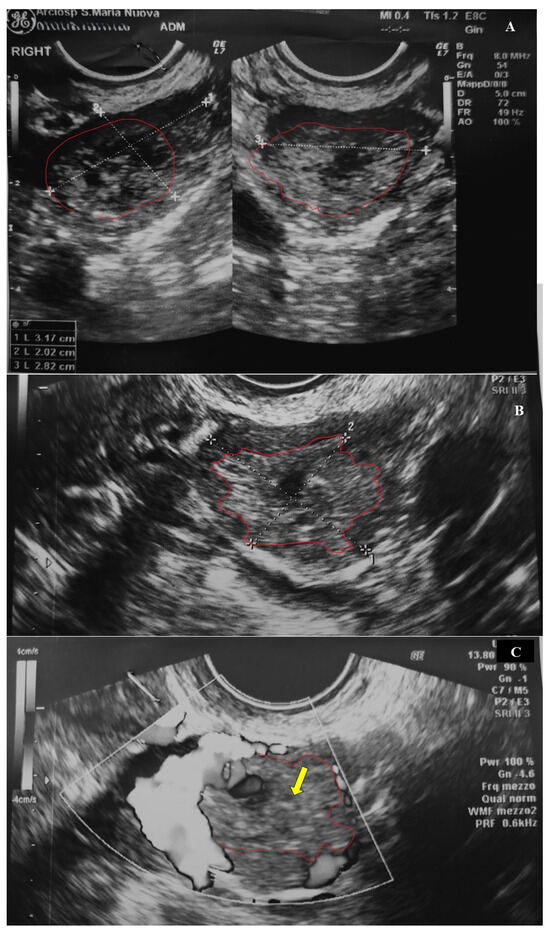

2.1. Clinical History